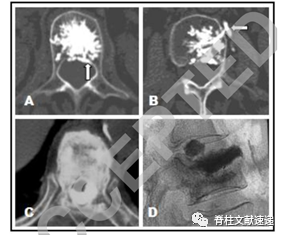

该文献作者在Yeom等人研究的基础上,将骨水泥渗漏重新分为四类(见下图)。

图注:图A:通过椎基静脉孔渗漏(B型);图B:通过节段静脉渗漏(S型);图C:通过椎体皮质骨折处渗漏(C型);图D:该型为文献作者新加的分类,骨水泥渗漏到椎间盘内(D型),并将C型渗漏定义为骨外非椎间盘渗漏。